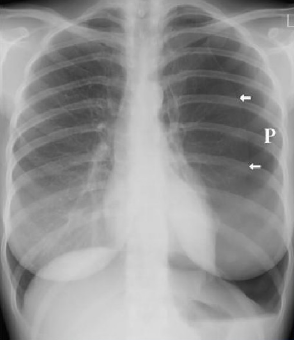

与其他致命性胸痛不同的是,气胸的诊断要简单得多。疑似气胸患者,进行常规胸片或胸部CT检查

,在影像学上见到肺野中纹理消失和被压缩的肺与气体之间形成的气胸线,就可确诊气胸(见图8)。

图8 气胸的胸部X线表现(白色箭头所指为气胸线)